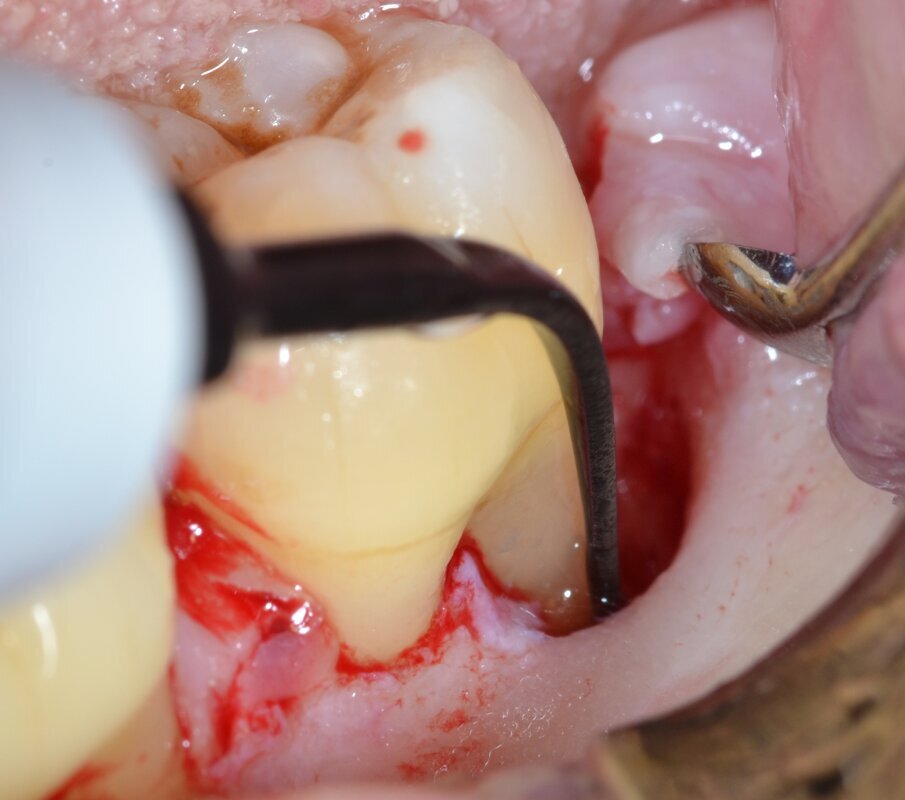

Dopo analgesia locale ottenuta per infiltrazione di Articaina cloridrato 40 mg con epinefrina 1:100.000 viene effettuata l’incisione di accesso secondo la tecnica denominata “Crestal Incision”4 per elevare un lembo a spessore totale che espone l’area interessata dal difetto (Fig. 5). Il debridement e la decontaminazione della superficie radicolare vengono effettuati per mezzo di inserti ultrasonici dedicati (Figg. 6, 7); al completamento di questo tempo chirurgico il difetto è innestato con biomateriale eterologo protetto da una membrana di tipo riassorbibile in pericardio di origine animale che viene fissata sulla cresta ossea mediante pins in titanio allo scopo di stabilizzare il coagulo e guidare la rigenerazione tissutale all’ interno del difetto. La ferita chirurgica è suturata con un filo riassorbibile 6/0 in PGA (Figg. 8-12).

Fig. 6 - Debridement del difetto intraosseo e decontaminazione della superficie radicolare mediante ultrasuoni (aspetto buccale).